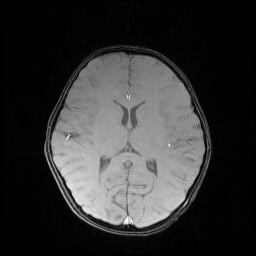

We illustrate with reconstructions for three CS-MRI methods: TLMRI (transform learning MRI) [25], PANO (patch-based nonlocal operator) [23] and GBRWT (graph-based redundant wavelet transform) [14]. The PANO and GBRWT models achieve impressive reconstruction qualities because they use an nonlocal prior and adaptive graph-based wavelet transform to exploit image structures. In TLMRI, the sparsifying transform learning and the reconstruction are performed simultaneously in more efficient way than DLMRI [24]. The three methods represent the state-of-the-art performance in the non-deep CS-MRI models. In Figure 2, we show the reconstructions error for zero-filled (itself a potential reconstruction “algorithm”), TLMRI, PANO and GBRWT on a complexed-valued brain MRI using 30%percent3030\% Cartesian under-sampling. The error display ranges from 0 to 0.2 with normalized data. The parameter setting will be elaborated in the Experiment Section V.

We also consider the deep learning DC-CNN model [26] as the guide module. We also give the reconstruction error in Figure 2. We observe the zero-filled, TLMRI, PANO, GBRWT and DC-CNN models all suffer the structural reconstruction errors, while the DC-CNN model achieves the highest reconstruction quality with minimal errors because of its powerful model capacity. Another advantage of this CNN model is that, once the network is trained, testing is very fast compared with conventional sparse-regularization CS-MRI models. This is because no iterative algorithm needs to be run for optimization during testing since the operations are a simple feed forward function of the input. We compare the reconstruction time of TLMRI, PANO, GBRWT and DC-CNN for testing for Figure 2 in Table I.

Figure 2: The reconstruction error of a brain MRI using zero-filled, TLMRI, PANO, GBRWT and DC-CNN under 1D 30%percent3030\% under-sampling mask.